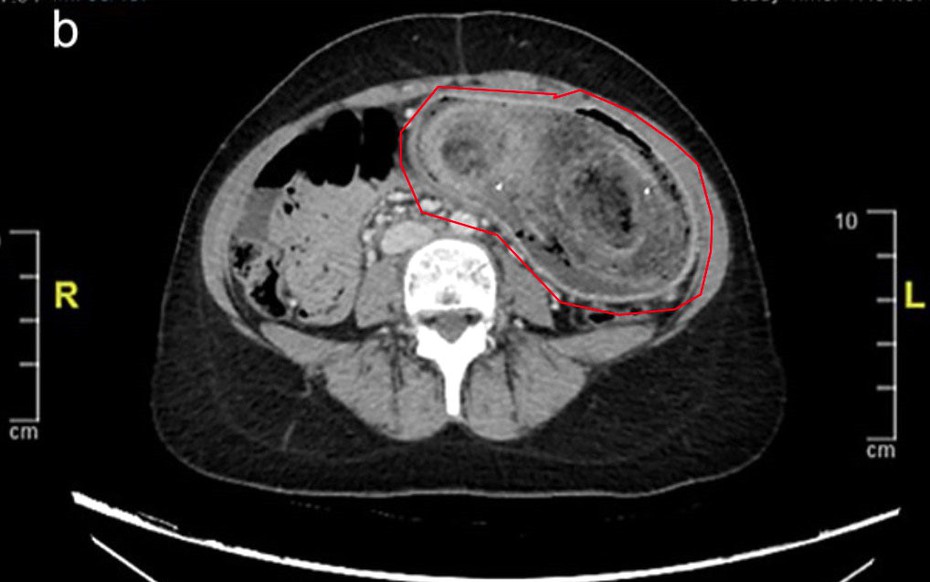

Trong khi tất cả các xét nghiệm trong phòng thí nghiệm đều bình thường, kết quả chụp CT xác nhận rằng búi tóc khổng lồ đã kéo dài từ dạ dày đến tá tràng.

Do kích thước của khối tóc, việc loại bỏ bằng phương pháp nội soi là không thể nên nữ bệnh nhân đã phải trải qua phẫu thuật mở dưới gây mê toàn thân.

Búi tóc lớn được lấy ra cẩn thận và vẫn còn nguyên vẹn. Và sau 3 giờ đồng hồ, dị vật đã được lấy ra an toàn.